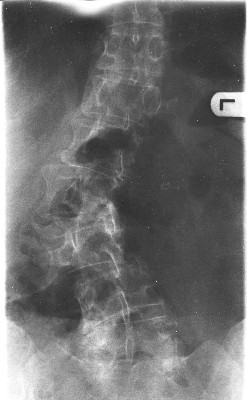

Gestern war ich noch mal bei dem Doc und ließ mir stärkere Schmerzmittel, eine Lumbal-Bandage verordnen. Die Röntgenbilder habe ich auch mitbekommen und kann somit hier mal ein Foto zeigen. ob man was erkennnen kann?

Auf dem Röntgenbild ist eine deutliche Skoliose zu erkennen, du solltest dich schleunigst in die Behandlung eines Spezialisten begeben und dich nicht länger mit deinem "0815-Orthopäden" rumplagen. Auf den Aufnahmen fehlt der obere Teil der BWS und die HWS- Du brauchst also unbedingt eine Wirbelsäulenganzaufnahme im Stehen, damit du den Zustand deiner kompletten(!) Wirbelsäule kennst. Wer weiß, wie dein thorakaler Gegenbogen aussieht!?

Man erkennt auf deinem Röntgenbild, dass du eher eine degenerative Skoliose hast, inkl. Gleitwirbel. Ich glaube nicht, dass du da allein mit Muskelaufbau weiterkommst.